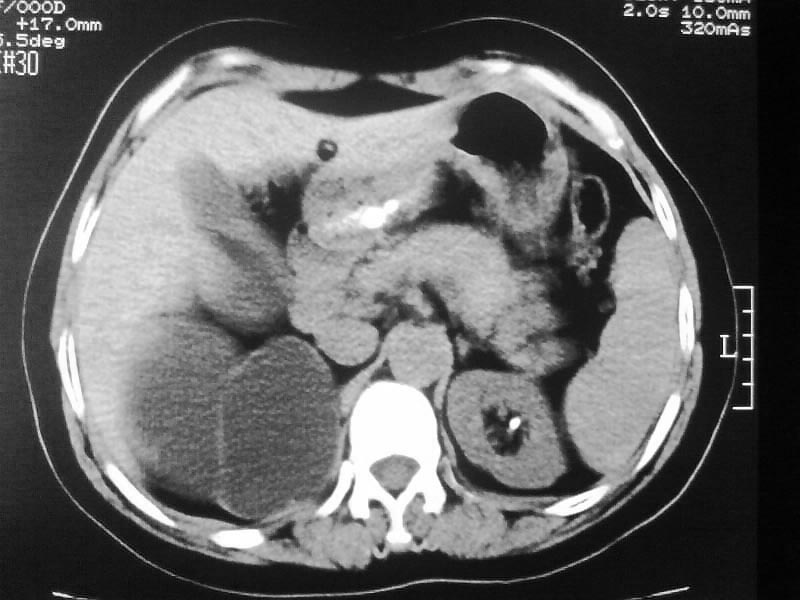

标题: CT20044:女,45岁,腰痛2年,双肾结石,右输尿管结石,右肾重度积 [打印本页]

标题: CT20044:女,45岁,腰痛2年,双肾结石,右输尿管结石,右肾重度积

支持双肾结石、右输尿管上端结石,右肾重度积水

支持 右肾结石、右输尿管上端结石,右肾重度积水。

支持双肾结石、右输尿管上端结石,右肾重度积水。